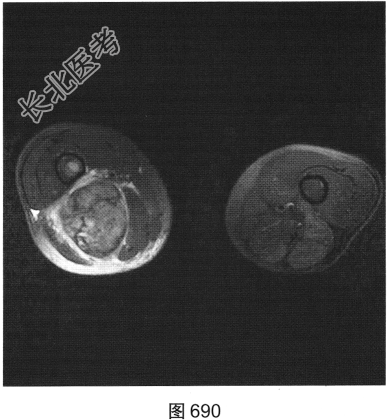

- 多项选择题3.[提示]为进一步明确诊断,患者进一步行CT及MRI检查, 如图686~图691所示。患者CT及MRI的阳性影像表现有( )

A、T2压脂序列上肿块内可见条状高信号

B、右大腿后方肌群内见肿块影

C、T1WI及T2WI均表现为实性肿块,均以等信号为主

D、T2压脂序列呈高信号,周围见明显水肿信号

E、肿块边界较清,密度较均匀

F、肿块周围肌间隙清晰,邻近组织呈受压改变

G、T2WI上可见斑片状稍高信号及低信号分隔

关注下方微信公众号,搜题查看答案